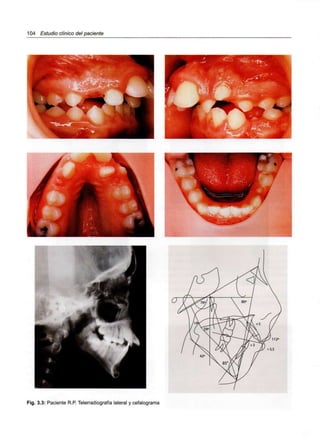

ESTUDIO CLÍNICO DEL PACIENTE

Introducción

Estética facial

Examen bucodental

Examen funcional